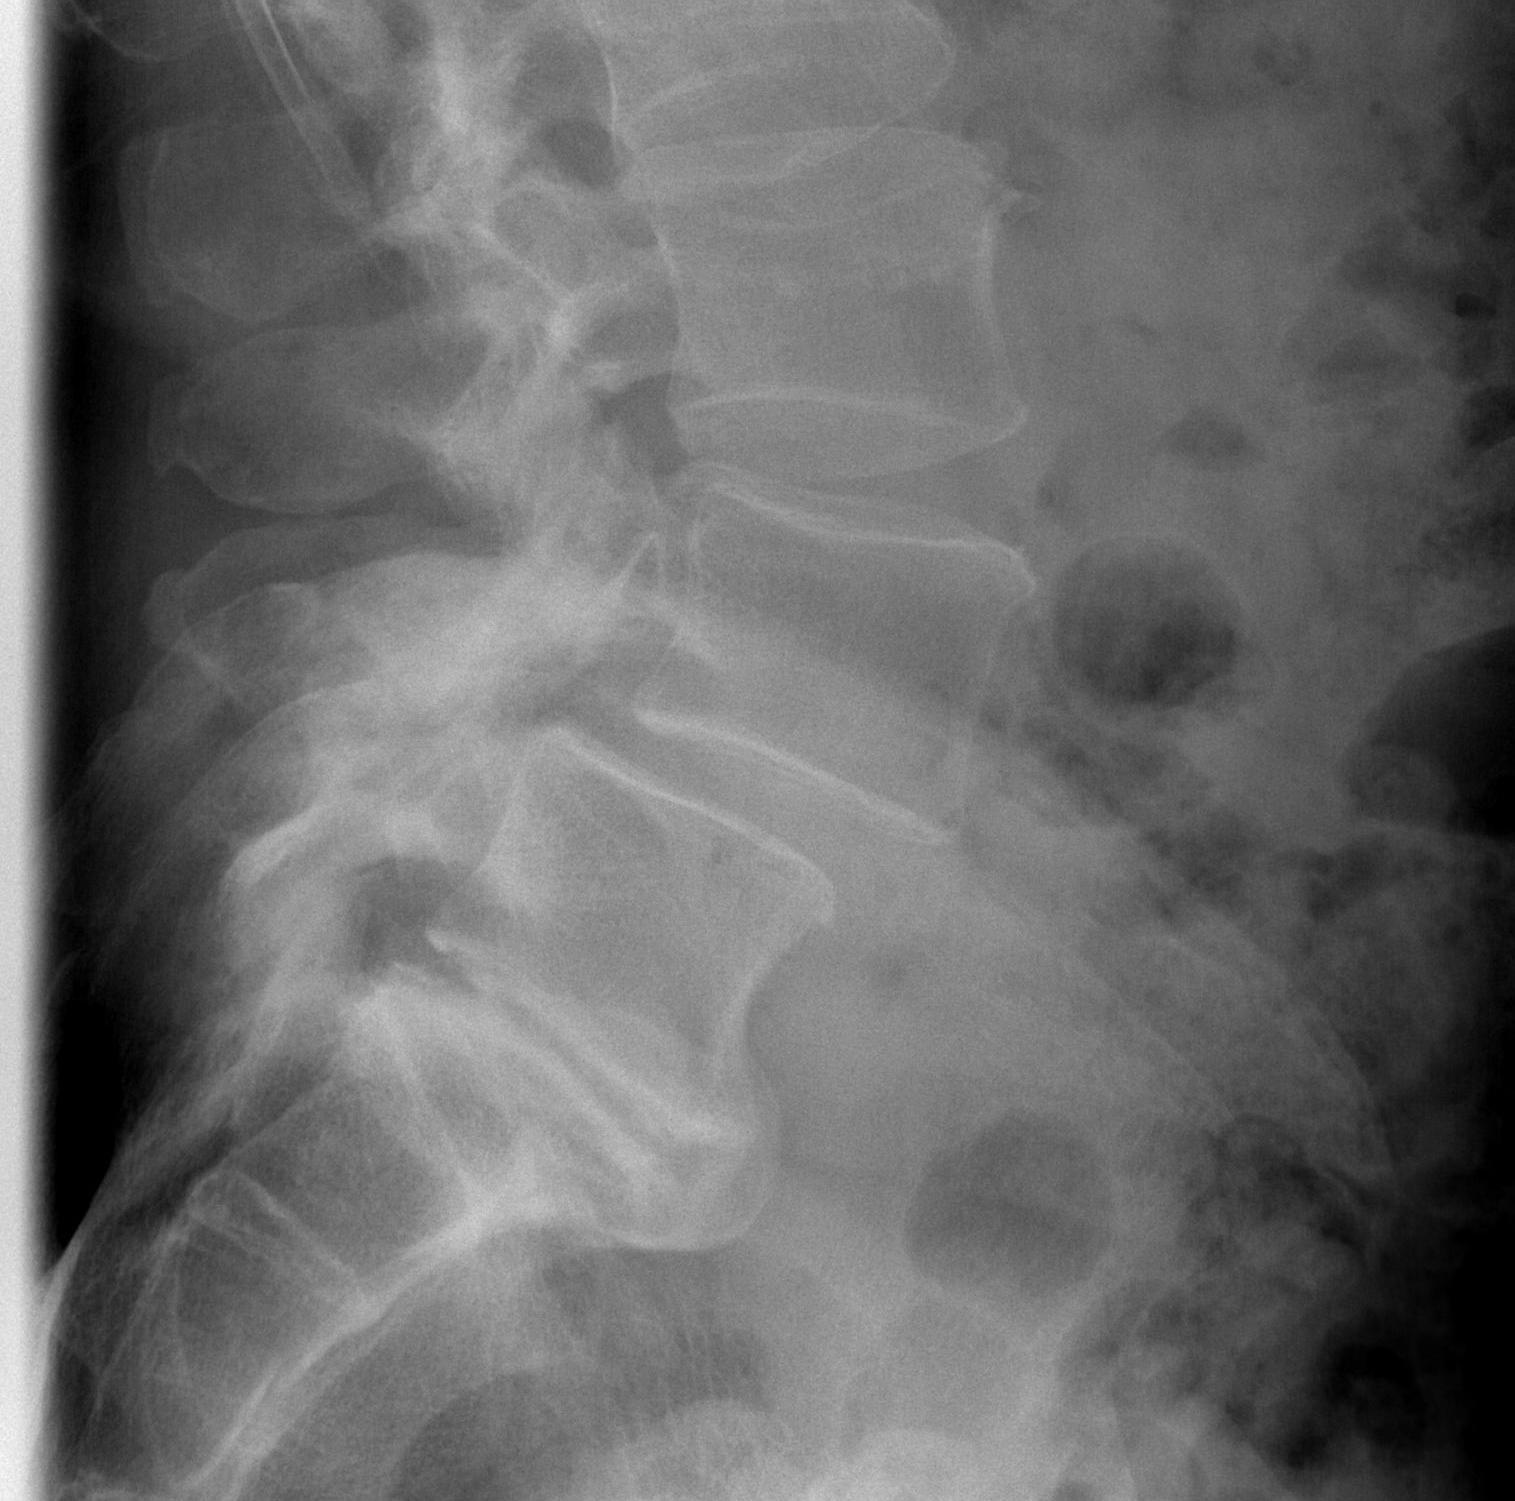

- sickling occurs with relative hypoxia

- trapped in blood vessels

- necrosis & pain